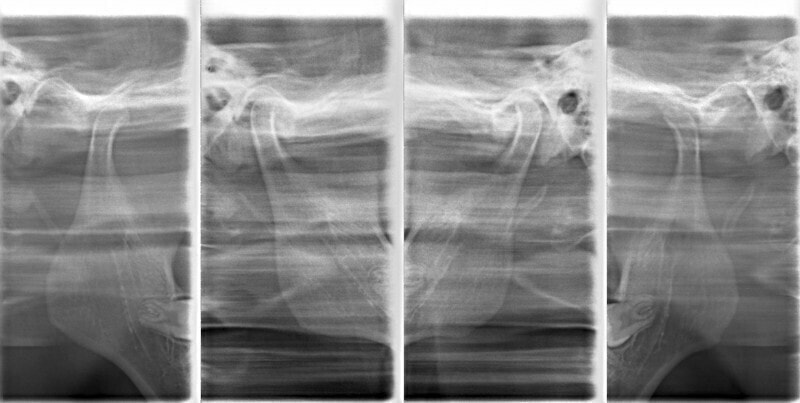

成人の反対咬合なので、少し顎関節にダメージはありますが、重症ではありません。

治療中のレントゲンです。

7番、8番の状態や歯根のパラレリング(平行性)をチェックしています。

左上2番の歯根の状態もなんとかもちそうです。

上顎劣成長症例ですが、鼻腔の状態も悪くありません。

特に左側の咬合時の顎関節の位置に改善が認められます。